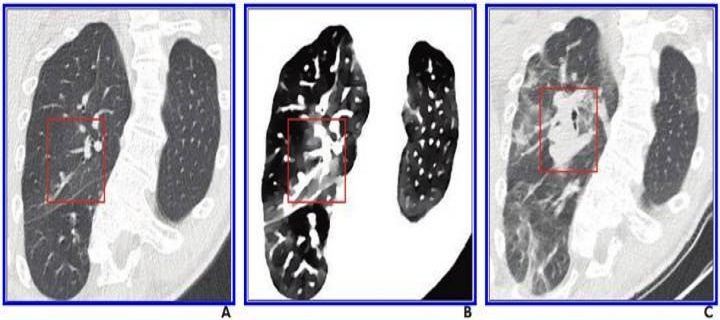

در هر چهار بیمار، آسیب ریه در تصاویر چگالی الکترون در مقایسه با سیتی اسکن معمولی بارزتر بود و این موضوع در پیگیری سیتی اسکن معمولی به طور واضح تأیید شد.

نتایج نشان میدهد که تصویربرداری با تراکم الکترون، ارزیابی زود هنگام از ریه را بهبود میبخشد که این مزیت در سی تی اسکن معمولی وجود ندارد.